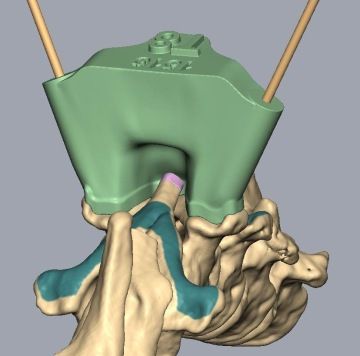

Veterinární chirurgové se učí od chirurgů lidských. Postupy aplikované na humánního pacienta se adaptují na pacienta zvířecího. Veterinární neurochirurgové umí odstranit nádor z mozku, operovat vyhřezlý meziobratlový disk, stabilizovat nestabilní páteř pomocí 3D tištěných operačních šablon.

Počítačové plánování stabilizační spinální chirurgie

Jedny z nejnáročnějších operací jsou zákroky na deformované páteři francouzských buldočků a mopsů. Vyžadují předchozí CT a MRI vyšetření, speciální 3D tištěné vrtací šablony pro bezpečné usazení implantátů a v zásadě vytvoření nové podpůrné páteře z polymetylakrylátu (kostní cement). Takové zákroky trvají i několik hodin a vyžadují extenzivní plánování a maximální soustředění celého operačního týmu během celého zákroku.